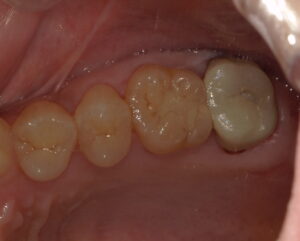

患者さんは30代女性。症状は特にありませんが、定期健診で来ていただいた時に直感で左上6番目の遠心が何となく怪しいと感じました。写真からはほぼわかりません。